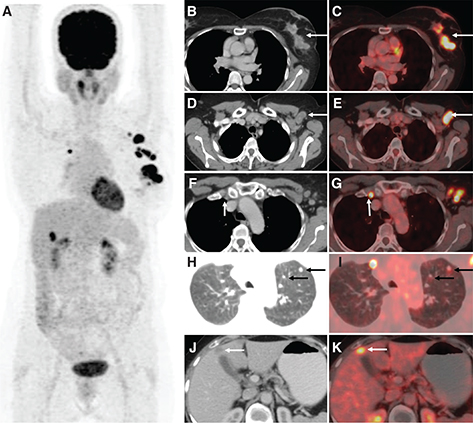

Fig 2

Figure 2. 18F-FES PET/CT in carcinoma breast. 18F-FES PET/CT in a patient with initially diagnosed left breast invasive ductal carcinoma (IDC), cT1cN0, ER+/PR+/HER-2 negative, Ki67 11%. Initially declined treatment and now with bilateral breast masses with Ki67 20%, bilateral lymphadenopathy, and pulmonary nodules. Images include: (A) axial CT, (B) axial FES PET, (C) fused axial PET/CT, (D) maximum intensity projection (MIP) image, (E) axial CT, (F) axial FES PET, (G) fused axial PET/CT, and (H) MIP image. 18F-FES PET/CT demonstrates increased FES uptake in the bilateral breast masses (images A-D), lymph nodes in the bilateral axillae, subpectoral regions, and mediastinum (images E-H), and bilateral pulmonary nodules (lung windows not included).